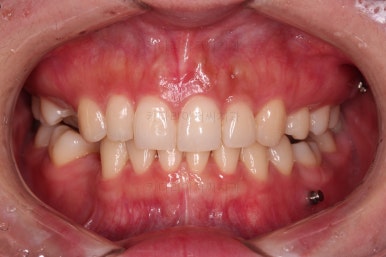

초진 시 입안의 모습인데요.

왜 그런지 비밀이 풀리는 것 같죠?

윗니는 한 쪽이 치아 2개가 결손이면서 유치가 하나 남아있고요.

아랫니는 한 쪽은 1개, 반대편은 2개 치아가 결손이었습니다.

도합 5개의 치아가 결손이었는데요.

결손 위치의 갯수가 위아래 좌우 다 달라서 중앙선이 맞을래야 맞을 수가 없는 상황이었죠.

결손치아 주위 치아들은 쓰러지고 비틀어져 있어서 장기적으로 좋지 못한 상황이었고요.

좀 더 디테일하게 윗니 작은 앞니 1개가 왜소치아라서 치아 크기도 맞지 않은 상황이었습니다.